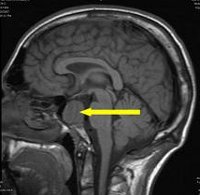

МРТ гипофиза

МРТ гипофиза. Томографическое исследование гипофизарных структур на основе явления ядерного магнитного резонанса. Сегодня это ведущий метод тестирования гипофиза и турецкого седла. Это позволяет с высокой точностью распознавать объемные процессы в турецкой седловой зоне и проводить дифференциальную диагностику (аденома, пролактинома, микроаденома, рак). МРТ гипофиза имеет особое значение при обнаружении микроаденом, которые из-за их небольшого размера не диагностируются другими методами. Безопасно, безболезненно. Это не сделано с металлическими имплантатами вокруг черепа.

МРТ гипофиза показана пациентам, у которых в анализе крови выявляется высокий уровень гормонов гипофиза (например, пролактина, гормона роста, тиреотропного гормона, АКТГ). В неврологии МРТ используется для диагностики злокачественных и доброкачественных опухолей гипофиза, определения их размера, распространенности, структуры и точного локализации. При использовании других методов микроаденомы гипофиза диаметром менее 10 мм часто остаются незамеченными. С помощью МРТ можно надежно обнаружить опухоли размером от 6 до 10 В большинстве случаев дополнительная МРТ используется во время МРТ гипофиза. Это необходимо для дифференциации гипофизарных образований, выявления злокачественных поражений и определения границ опухолевого процесса.